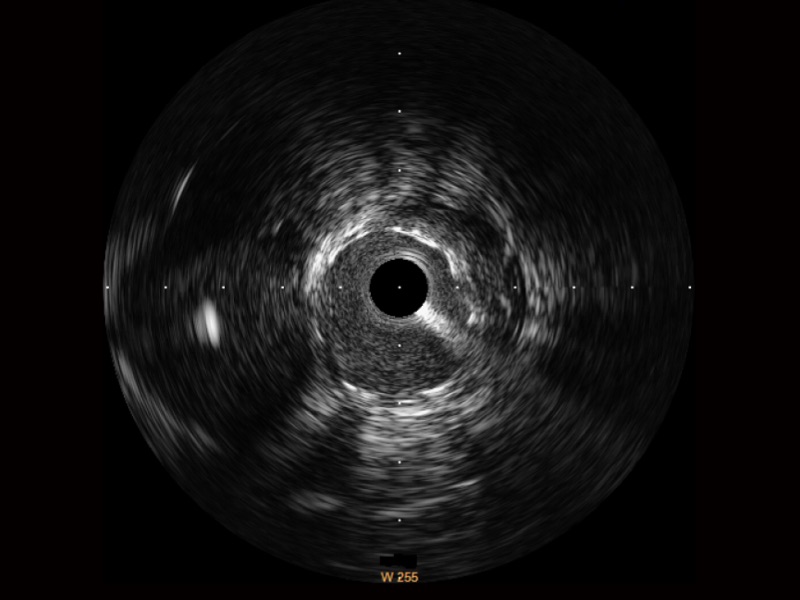

哈哈体育官网宽频IVUS图像

传统IVUS图像

对比传统IVUS导管成像,哈哈体育官网宽频IVUS图像的近场支架梁显影更细腻,远场中膜外血管仍清晰可辨,兼顾远中近,兼顾分辨力与穿透深度